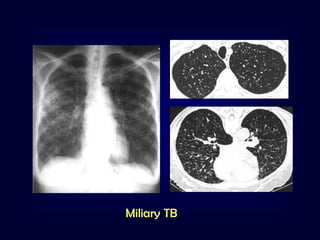

Nodular pattern [ multiple rounded opacities 110mm]

Miliary [1-2mm], the size of millet seeds

TB

Metastases

Pneumoconiosis

Sarcoidosis

Alveolar cell carcinoma



Hematogenous dissemination

Innumerable fine nodules

Uniform distribution

Mild thickening of

the interstitial lung markings

Miliary TB